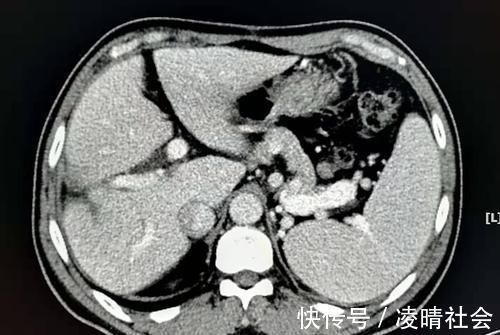

复查的CT片还能看到肝脏的手术豁口,人类的肝脏有很强的再生和代偿能力。这也是一位很成功的病人!